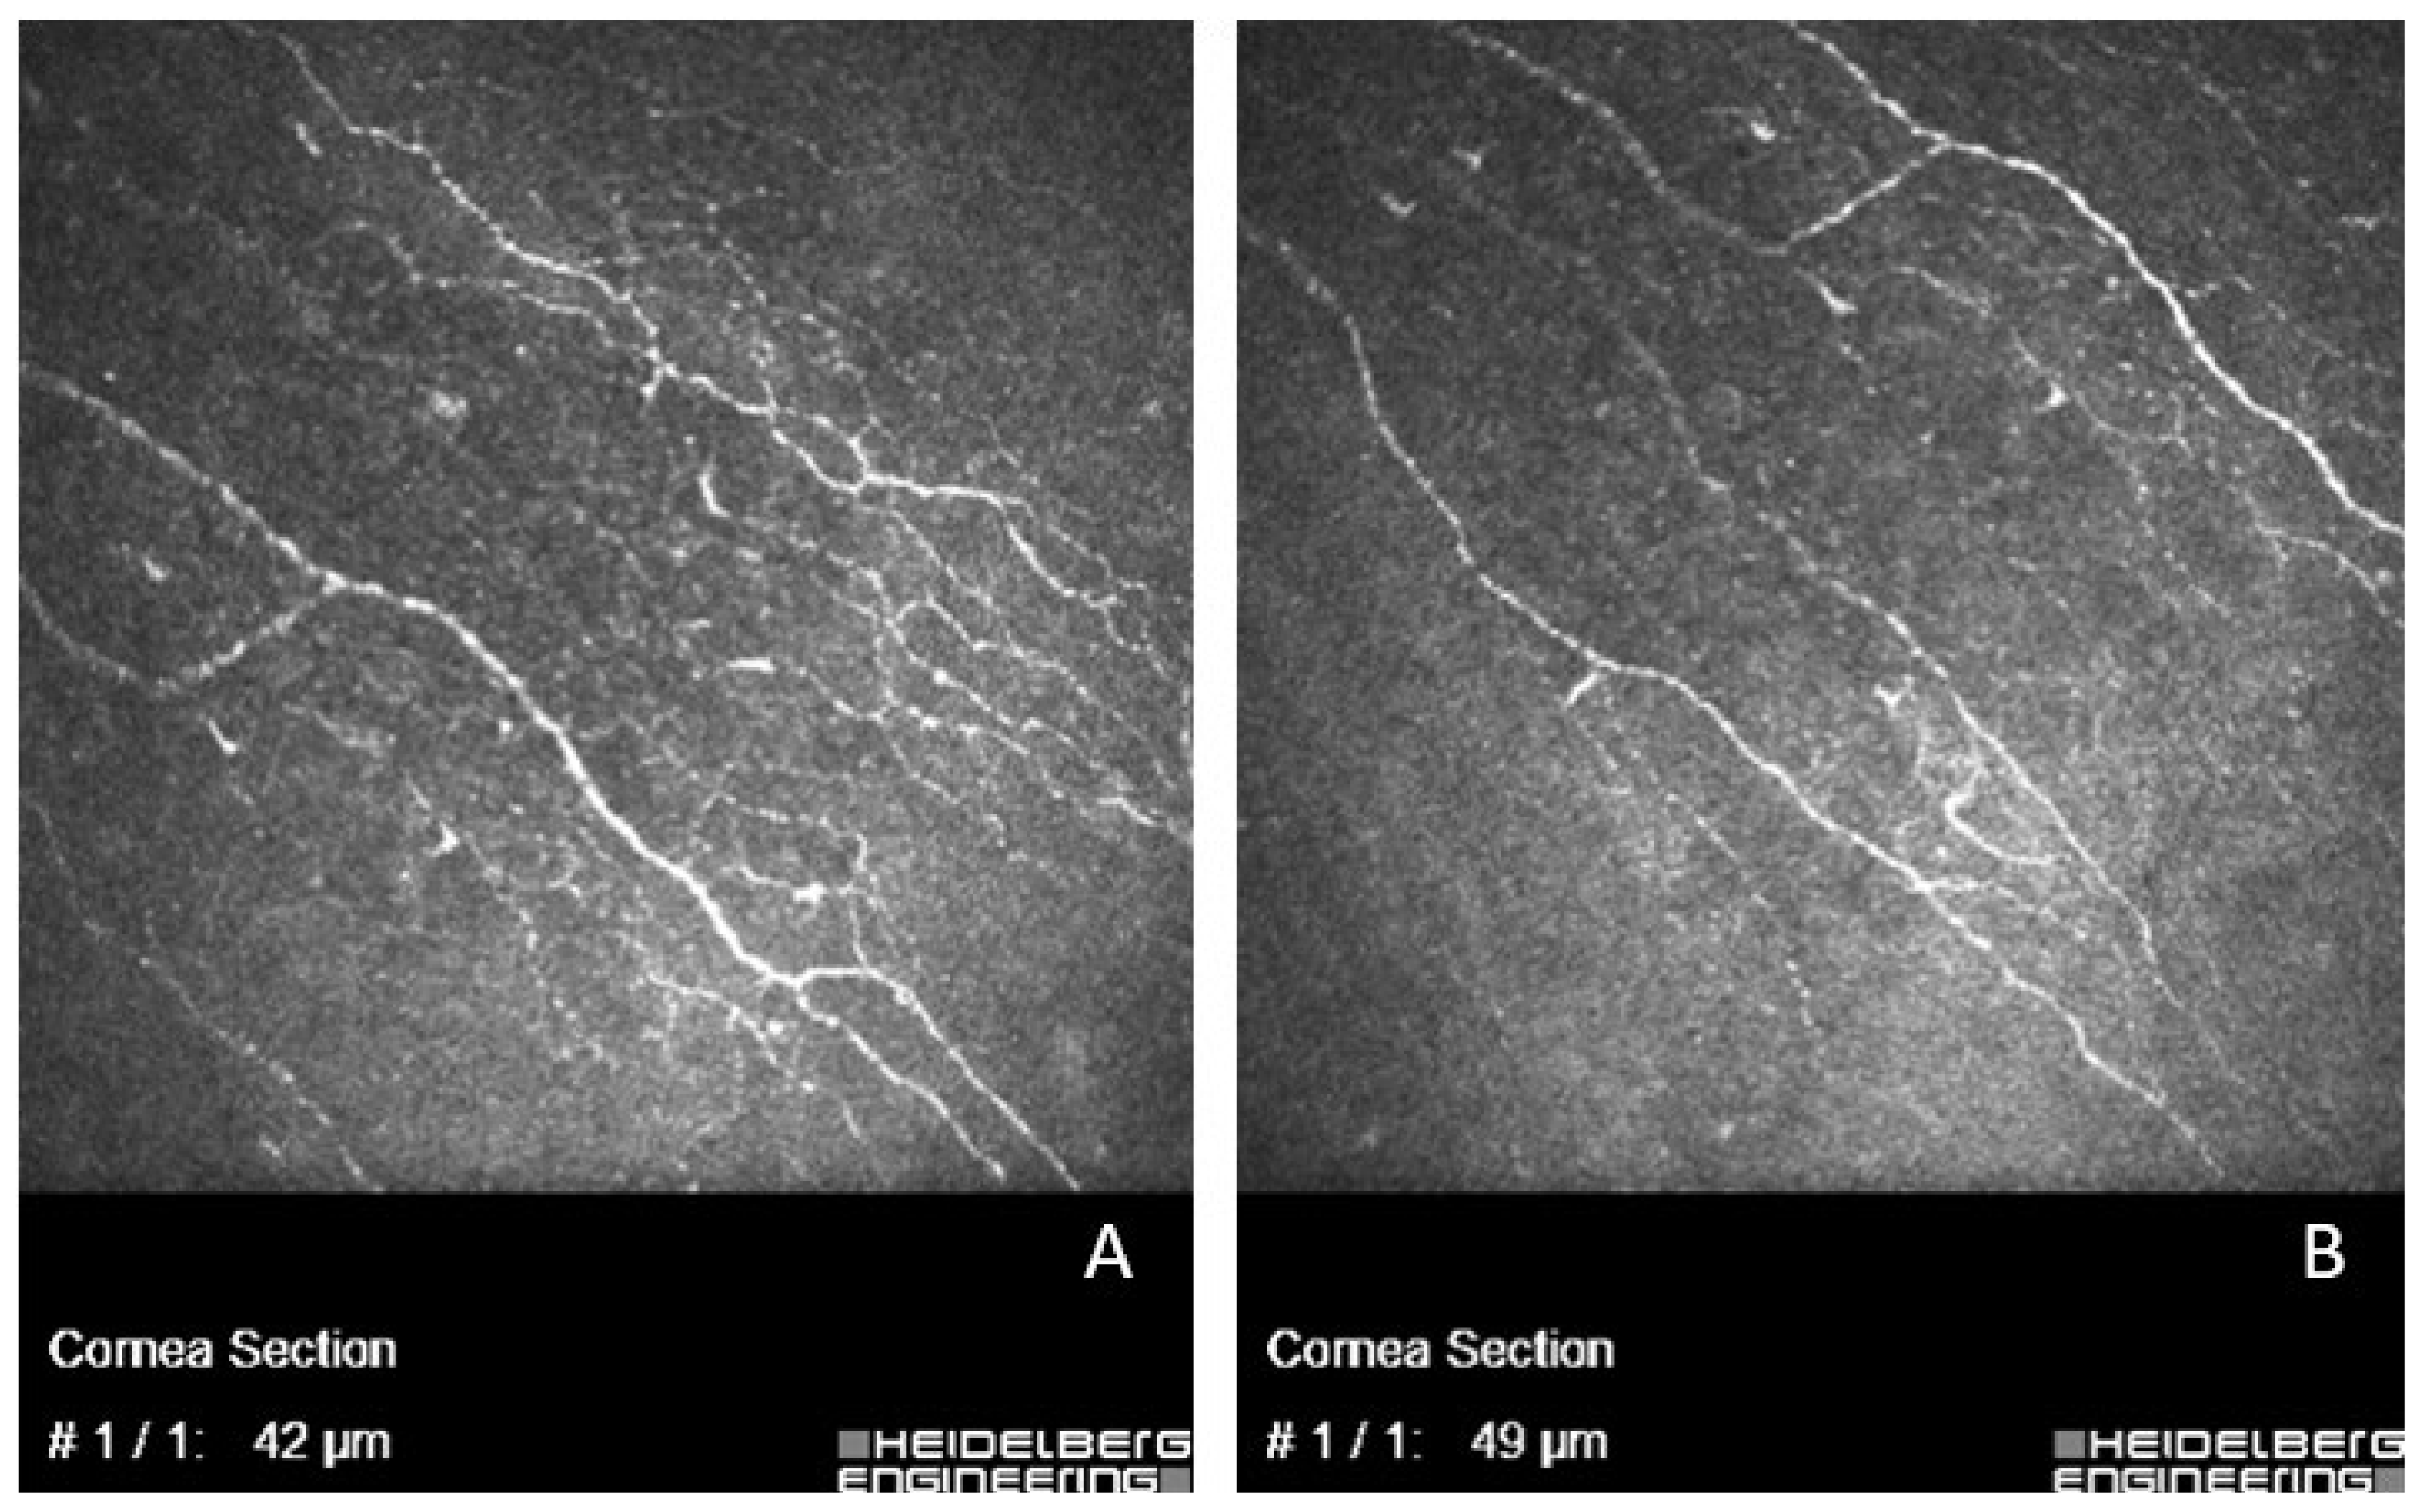

- In vivo confocal microscopy was carried out by the same investigator at the central cornea to evaluate it with laser scanning confocal microscope Heidelberg Retinal Tomograph (HRT II RCM Heidelberg Engineering Inc, Heidelberg, Germany; Rostock Cornea Module). The laser source is a diode laser at a wavelength of 670 nm. The acquired 2D images have a definition of 384 × 384 pixels over an area of 400 × 400 μm. Before the test, one drop of local anesthetic was instilled in the conjunctival sac (Proxymetacaine hydrochloride 0.5%). The single use contact element in sterile packaging (TomoCap) was used during the test which was lubricated with sterile gel (Carbomer 2.5 mg/g) for better image quality. In each case, another independent investigator picked from eight to 10 images which were analyzed with the Image J program (National Institutes of Health, Bethesda, Maryland, USA), Neuron J extension (Biomedical Imaging Group, Lausanne, Switzerland). The evaluation consisted of two parameters: the density of corneal nerves (it showed the length of nerve fibers in one square millimeter, mm/mm2) and the number of fibers (measured in one image). Confocal microscopy was conducted for not all the study participants because some patients refused to repeat this test after the cataract surgery, or images were not representable, so such cases (n = 26) were not included in the final analysis.